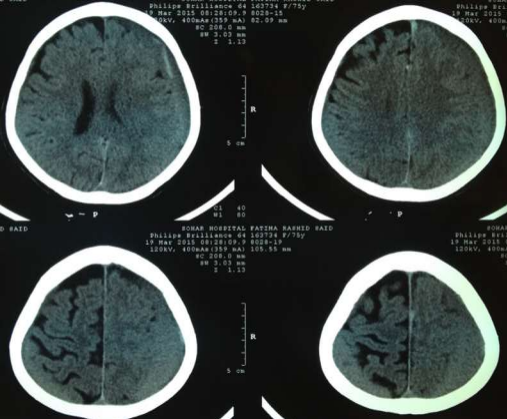

Fig 1,2,3,4,5,6,7,8,9,10,11,12,13,14,15

Thirty eight out of Eighty-two patients were treated conservatively and were studied (25 men; 13 females, mean age, 64.8 years). The average thickness of the hematoma was 18 mm, the mean midline shift was 4.7 mm, and the average attenuation value of bleed on computed tomography scan was 33.5. Thirty-eight were treated successfully with steroid treatment, whereas 44 patients required surgery. The female gender, less midline shift, less density (Hounsfield units) was noted to be associated with successful medical treatment. We propose a grading based on the total score given to the midline shift and density.

Figure 5

Figure 6

Figure 7

Figure 8